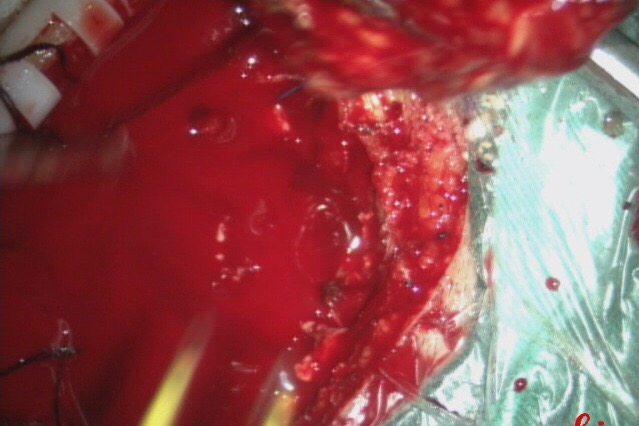

介入手术完成后,行开颅手术治疗。可直接切断经颈外动脉对瘤体的供血。

沿着肿瘤边缘分离肿瘤。

术中出血约1500ml.

完整切除肿瘤。

手术用时3小时55分钟.完整切除肿瘤。